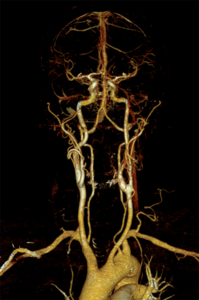

Aus den dabei gewonnen Schnittbildern sind computergestützte 2D- und 3D-Rekonstruktionen aller Regionen des Gefäßsystemes herstellbar. Dieses Untersuchungsverfahren kommt in unserem Zentrum bei der Diagnostik – Erweiterungen der Bauchschlagader oder andere Gefäße, Durchblutungsstörungen aufgrund von Gefäßeinengungen oder Verschlüssen sowie der Therapieplanung und Therapiekontrolle – zum Einsatz. Einen wichtigen Stellenwert hat die Computertomografie auch bei allen akuten Gefäßerkrankungen und Gefäßverletzungen.

Die Gefäßdarstellung erfolgt in einem modernen 48-Kanal-Magnetresonanztomografen (Siemens Area 48) der mit spezieller Hard- und Software für die Darstellung aller Gefäße des Körpers ausgerüstet ist. Dazu wird überwiegend ein gadoliniumhaltiges Kontrastmittel verwendet, welches meist über eine Armvene injiziert wird. Die Untersuchung dauert ca. 10 – 20 Minuten.

Neben der Erfassung von Veränderungen des Gefäßdurchmessers zur Beurteilung der Durchblutungsstörung, liefert uns diese Untersuchungsform auch wichtige Information zum Aufbau der Gefäßwände, zum Beispiel bei entzündlichen Gefäßerkrankungen und zum Nachweis von durchblutungsgestörtem Gewebe.